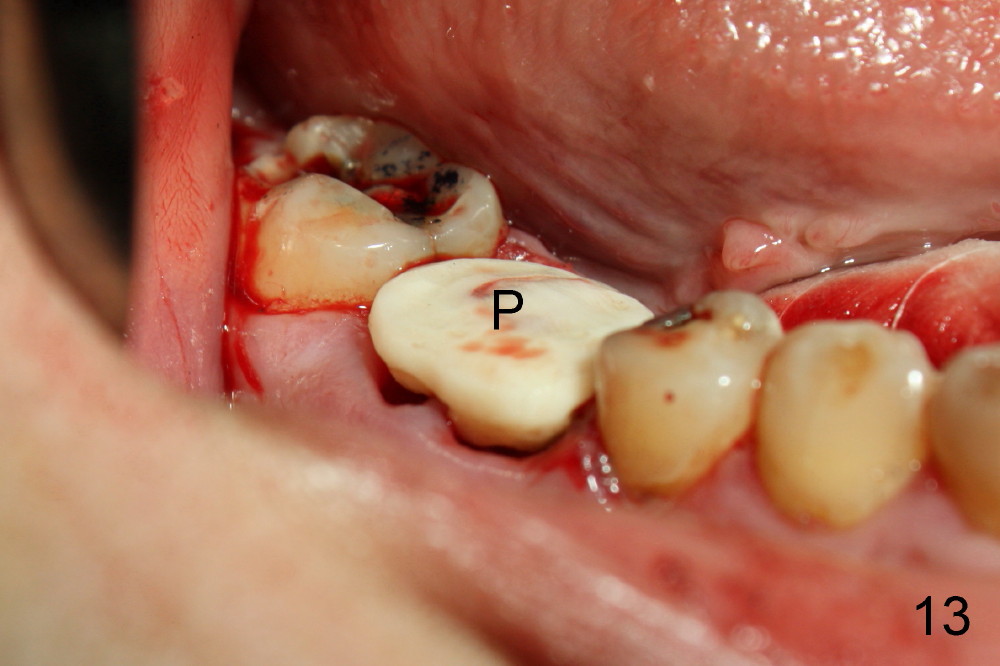

A 38-year-old lady agrees to have implant placement 7 years after loss of the crown of the lower right first molar (Fig.1,2). When the tooth is extracted, the septum is found to be low (Fig.3,4). To confirm it, a PA is taken (Fig.5). To initiate an osteotomy in the septum, it is trans-sectioned with thin osteotomes as shown in Fig.4 insert (black line). A 2 mm pilot drill is placed in the septum (Fig.6: P). The osteotomy is enlarged by 2.5-4.0 mm reamers (Fig.7,8), followed by insertion of 6x17 mm tapered tap at the depth 14 mm (Fig.9). The osteotomy is further enlarged by 4.5 and 5.0 mm reamers. A 6.0x14 mm one piece implant is placed initially. The trajectory is not ideal. A 6.0x14 mm one piece implant is placed initially. The trajectory is not ideal. The implant is removed from the osteotomy partially and reinserted with improved trajectory (Fig.11, compare to Fig.10 (red line)). Primary stability is high. There is not much bone mesiodistally so that the trajectory is easily changed in that direction. After abutment preparation, mixture of autogenous bone (harvested from reamers) and allograft is placed in the residual mesial and distal sockets (Fig.12). To contain the bone graft, an immediate provisional is placed (Fig.13 P). The occlusal plane of the provisional is significantly lower than that of the adjacent teeth to avoid micromovement of the implant. The patient is advised to eat soft food on the left side. Six days postop, the patient returns for prophy. The provisional is removed; the bone graft appears to be incorporating into the socket (Fig.14). After recementation, the provisional remains in place for 3.5 months; PA shows increased bone density in the mesial and distal sockets (Fig.15, compare to Fig.5,11). Due to insurance coverage, the patient defers fabrication of definitive restoration for at least 7 months. The immediate provisional is finally lost 8.5 months postop: the gingiva attaches to the 1-piece implant (Fig.16), while the density of the mesial socket increases (Fig.17 *) with formation of the cortex (lamina dura) coronally (v). Before the provisional (Fig.18 P) is removed for cementation of the definitive restoration, black shadow (*) is noted over the buccal gingiva. It is partially due to buccal placement (Fig.19) and partially due to buccal atrophy over a period of 10.5 months postop. How to prevent buccal placement? Positioning the first pilot drill in the septum buccolingually is a key. Eleven months post crown (Fig.20 C) cementation, the black shadow remains, but there is no tenderness. If the implant threads are immediately underneath the periosteum, there is tenderness.